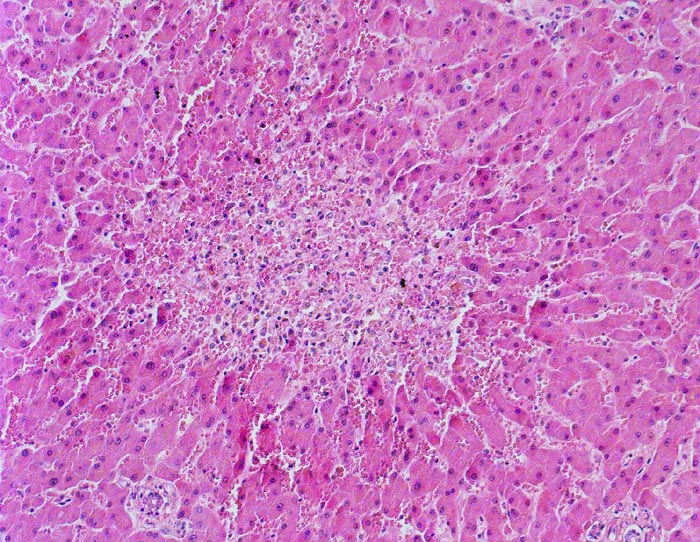

Einleitung

Linksherzversagen oder ein Schockzustand können zu einer hepatischen Minderperfusion mit ischämischen Koagulationsnekrosen der perivenulären Hepatozyten führen. Die Kombination von Hypoperfusion und retrograder Stauung (Rechtsherzversagen) führt zu zentrilobulären hämorrhagischen Nekrosen. Klinisch führen diese Nekrosen zu einer transienten geringen bis mässigen Erhöhung der Transaminasewerte, gelegentlich auch zu einem leichten Ikterus.

Metastasierendes Kolonkarzinom. Als Todesursache fanden sich nicht ganz frische zentrale und perizentrale Lungenembolien.